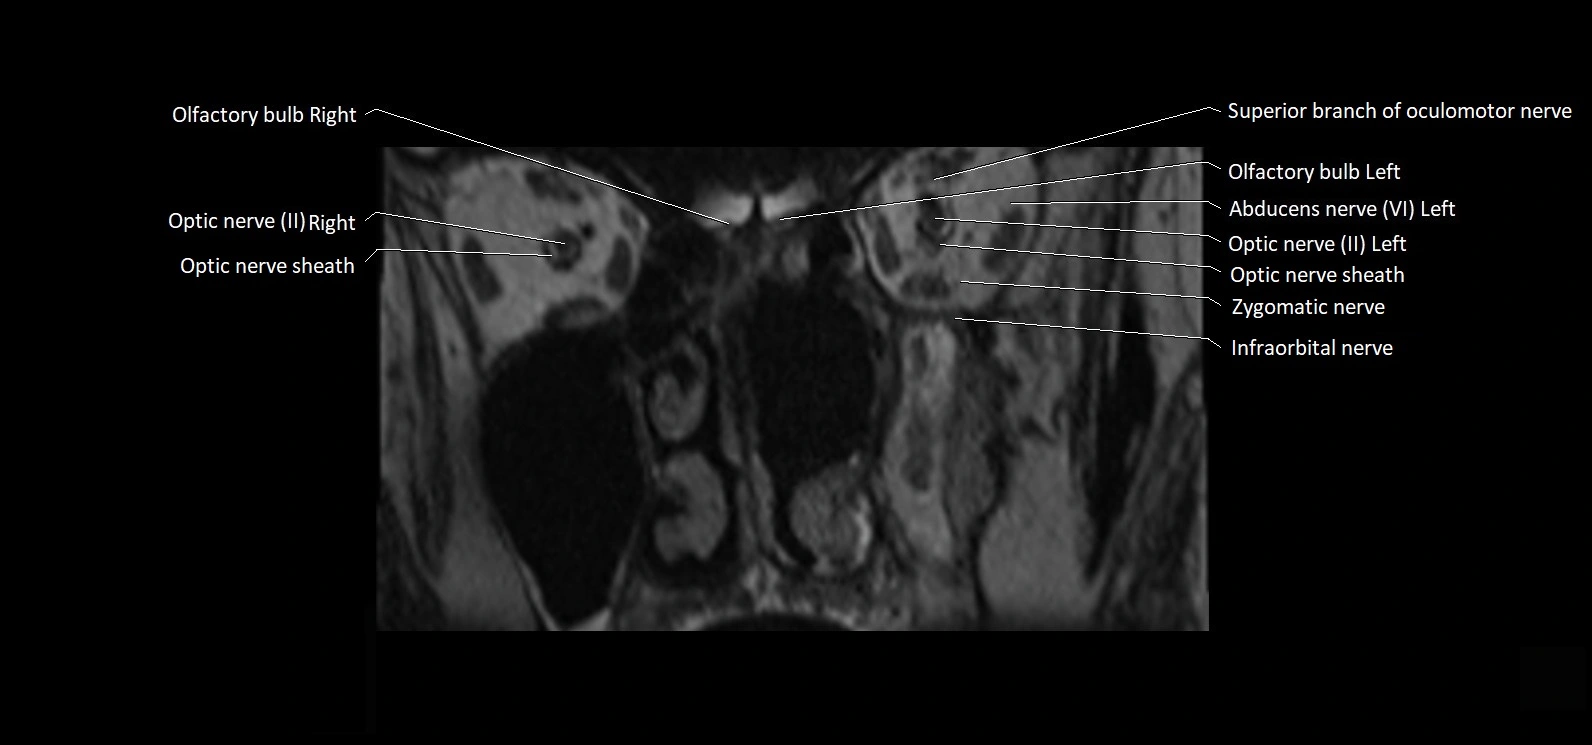

MRI Appearance

• The abducens nerve is a small, thin, linear structure

• Best visualized on high-resolution T2-weighted 3D MRI sequences (e.g., FIESTA or CISS)

• Seen as a hypointense (dark) line running from the brainstem at the pontomedullary junction, traversing the prepontine cistern, and entering Dorello’s canal under the petrosphenoidal ligament, then into the cavernous sinus, and finally the orbit

• May be challenging to visualize in standard MRI due to its small size

• Pathology may be inferred by absence, displacement, or enhancement of the nerve

MRI images

image